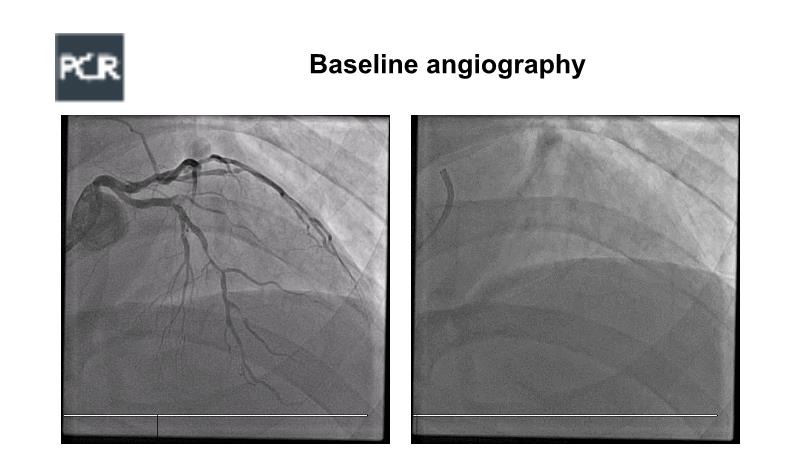

A hybrid approach in complex PCI: can DES and DCB be complementary?

Watch this case-based session to follow discussion about how to choose between DES & DCB, how both can be complementary in diffuse disease as well as in complex PCI, and how physiology and imaging can help guiding PCI, and follow a patient's treatment live.